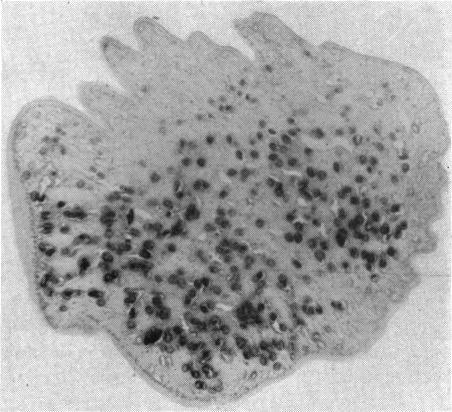

OCULAR SPARGANOSIS IN AN AFRICAN WOMAN.

Br J Ophthalmol. 1962 Feb;46(2):123-5. doi: 10.1136/bjo.46.2.123.

PMID:18170760